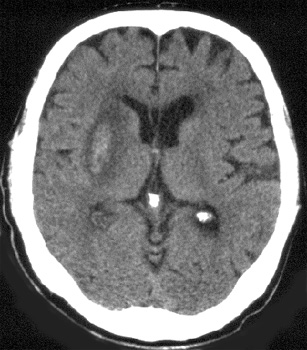

After 4 - 7 days the CT is characterized by:

- Gyral enhancement

- Persistent mass effect

In 1-8 weeks:

- Mass effect resolves

- Enhancement may persist